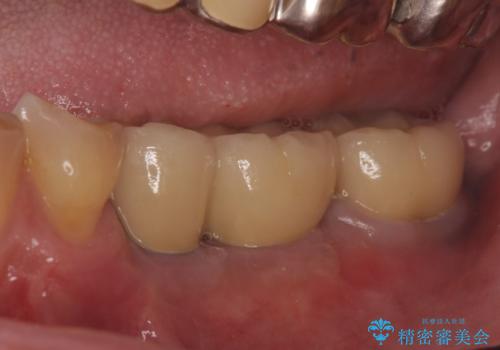

- 左下奥歯が虫歯で抜歯になってしまったため、インプラントにしたいといらっしゃった方の症例です。

欠損部位である左下5、6番目にインプラントを埋入し、オールセラミッククラウンによる補綴を行いました。

左下7番目は再根管治療を行い、オールセラミッククラウンによる補綴を行いました。